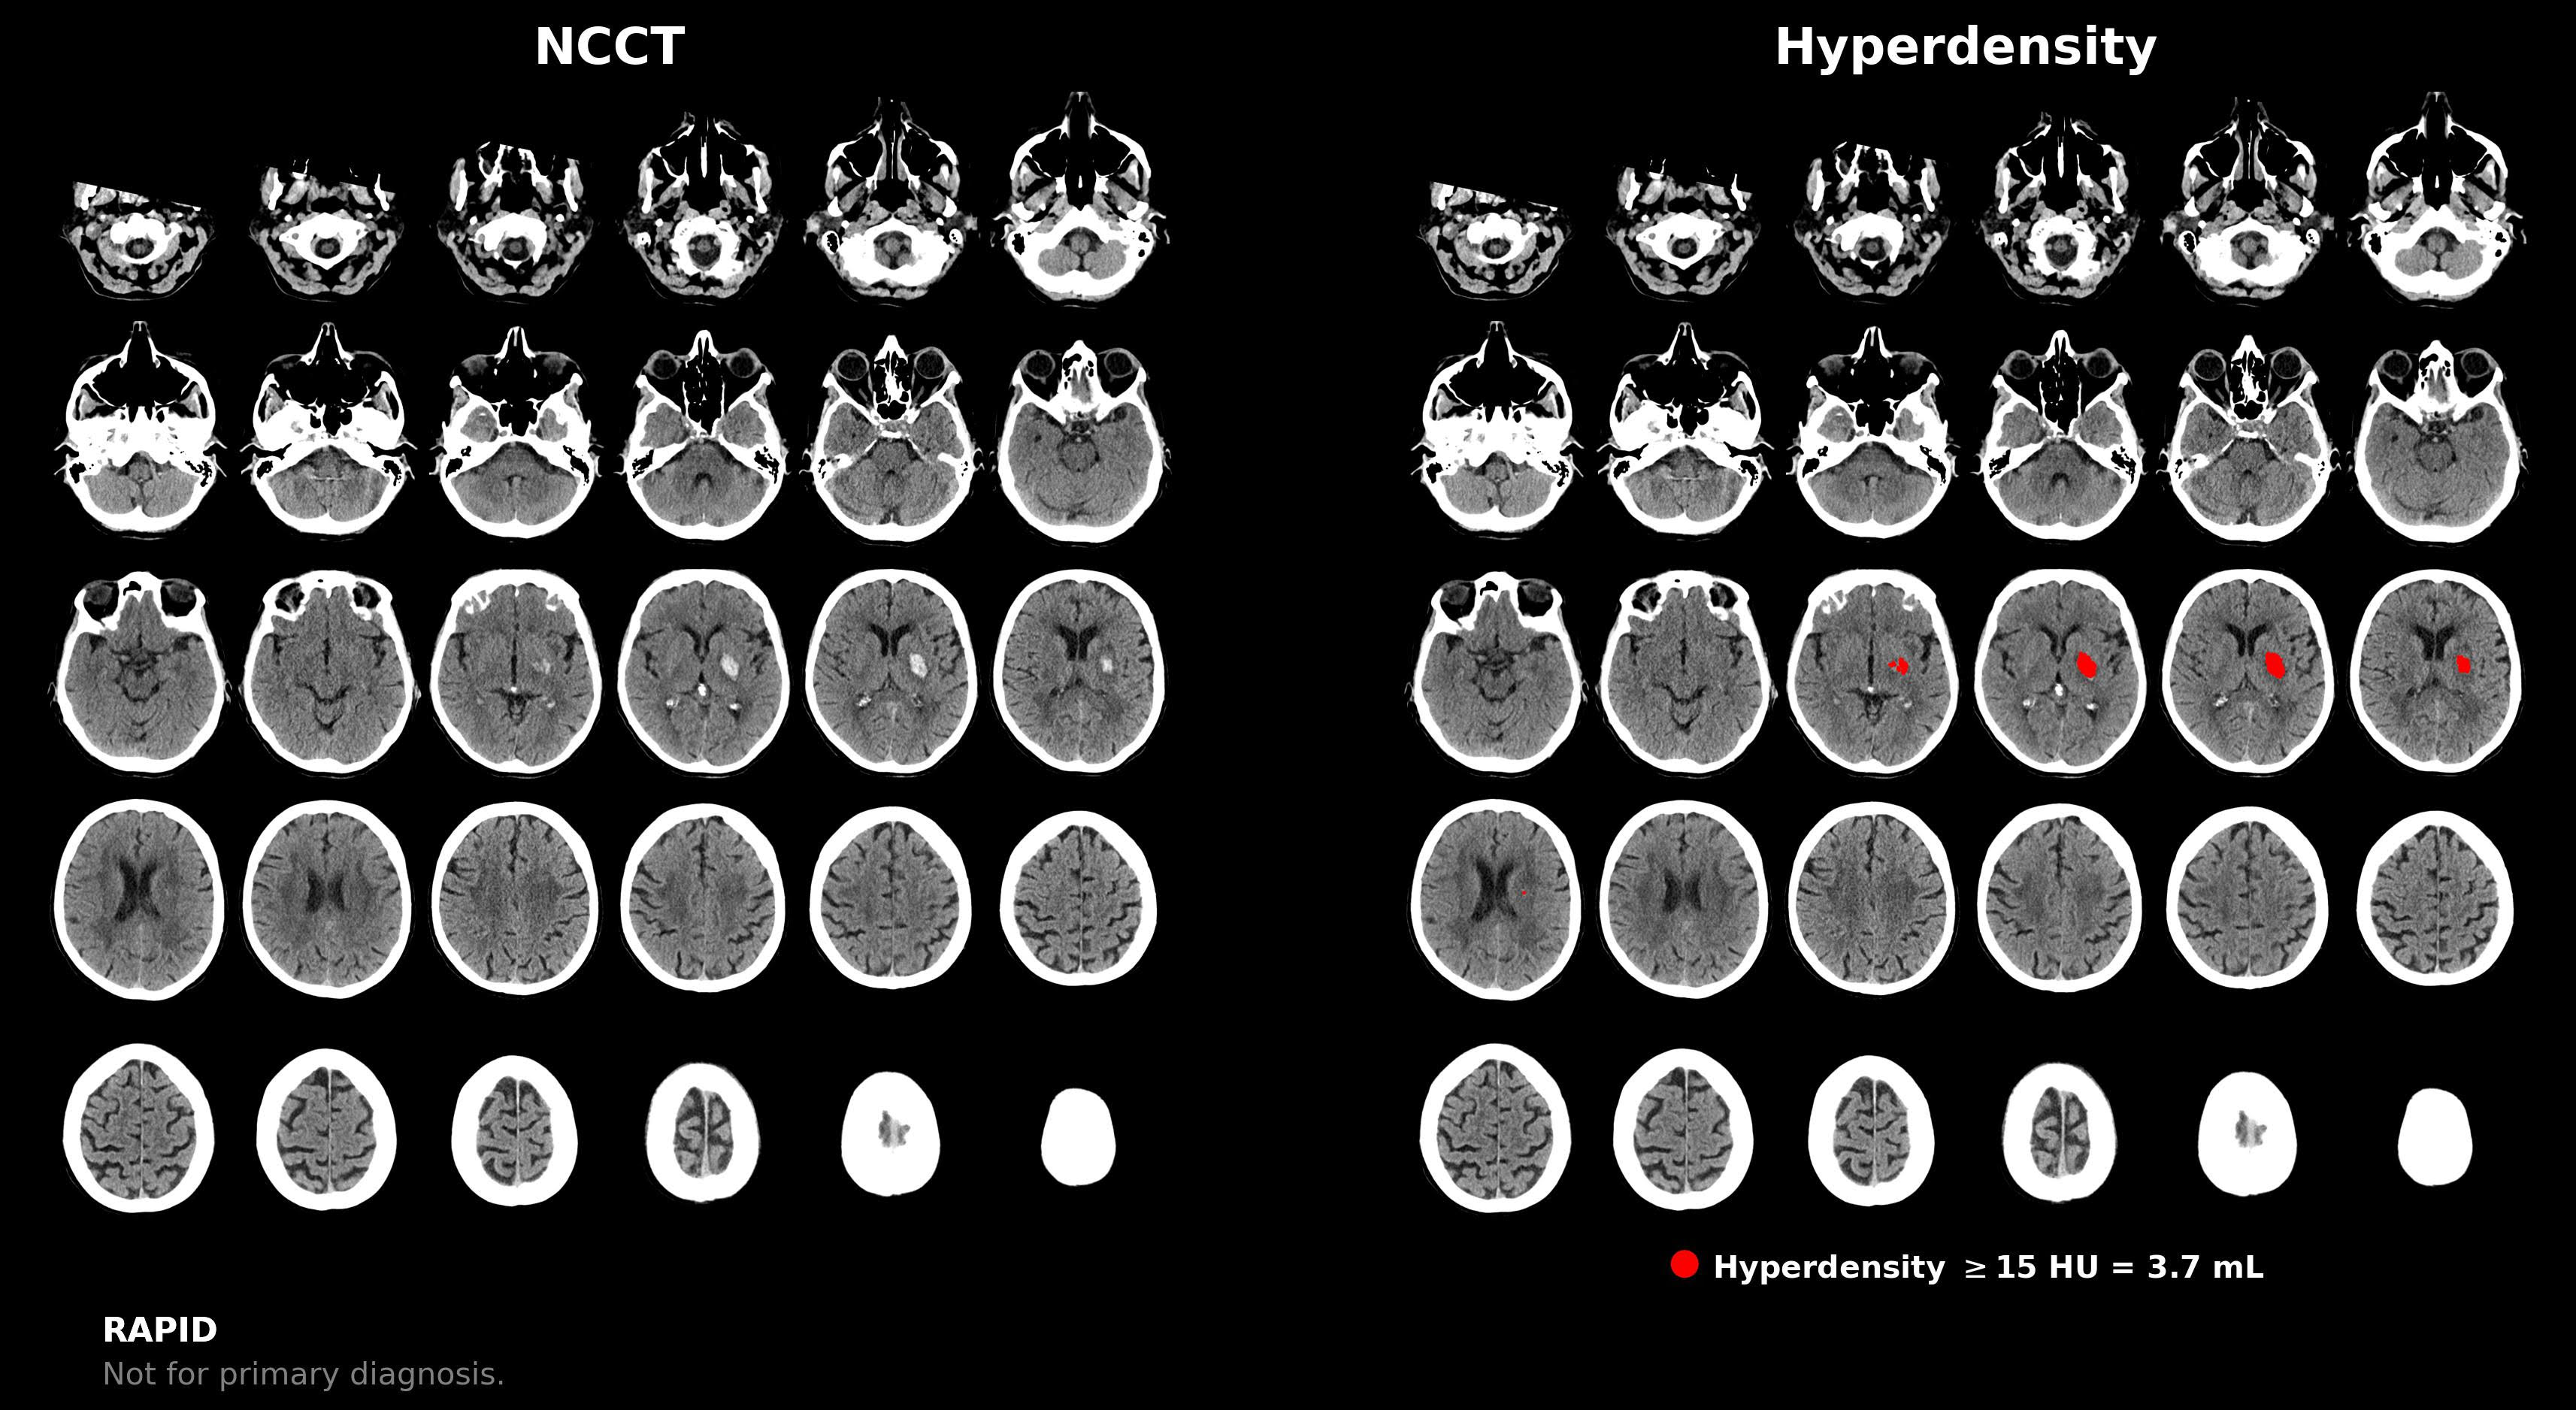

The advisory emphasizes that the computer-aided triage and notification (CADt) devices, many of which incorporate artificial intelligence (AI) or machine learning technology, are intended to aid radiologists in prioritizing the assessment of brain imaging that may reveal signs of large vessel occlusion (LVO).